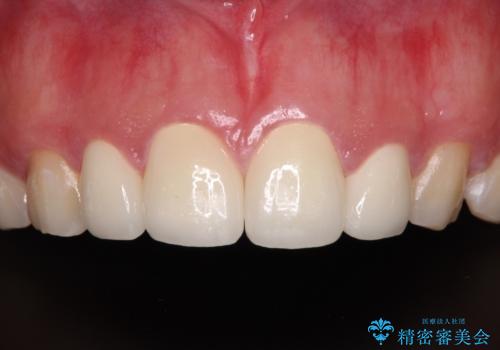

前歯の捻れは、オールセラミッククラウンよりも矯正治療による改善の方が、歯を削らなくて済むためお勧めとなります。

しかし、矮小歯の改善はオールセラミッククラウンでの補綴治療が必要であり、幅径のバランスを取る必要があるため、4前歯の補綴治療を選択しました。